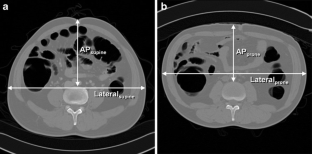

A search of our CTC and colonoscopy database found 37 patients (43 eligible lesions) who fulfilled the following criteria: colonoscopy-proven sessile polyps ≥6 mm in the straight mid-ascending colon, lesion visualisation in both supine and prone CTC, and optimal colonic distension. A coordinate system was developed to designate the polyp radial location (°) along the luminal circumference, unaffected by rotation of the torso. The degree/direction of polyp radial location change (i.e. ascending colonic rotation) between supine and prone positions correlated with anthropometric measurements.

Movement from supine to prone positions resulted in a change in the radial polyp location of between −23° and 79° (median, 21°), demonstrating external rotation of the ascending colon in almost all cases (2° to 79° in 36/37 patients and 42/43 lesions). The degree/direction of rotation mildly correlated with the degree of abdominal compression in the anterior-posterior direction in prone position (r = 0.427 [P = 0.004] and r = 0.404 [P = 0.007]).

The ascending colon was usually found to rotate externally as patients moved from supine to prone positions, partly dependent on the degree of abdominal compression.